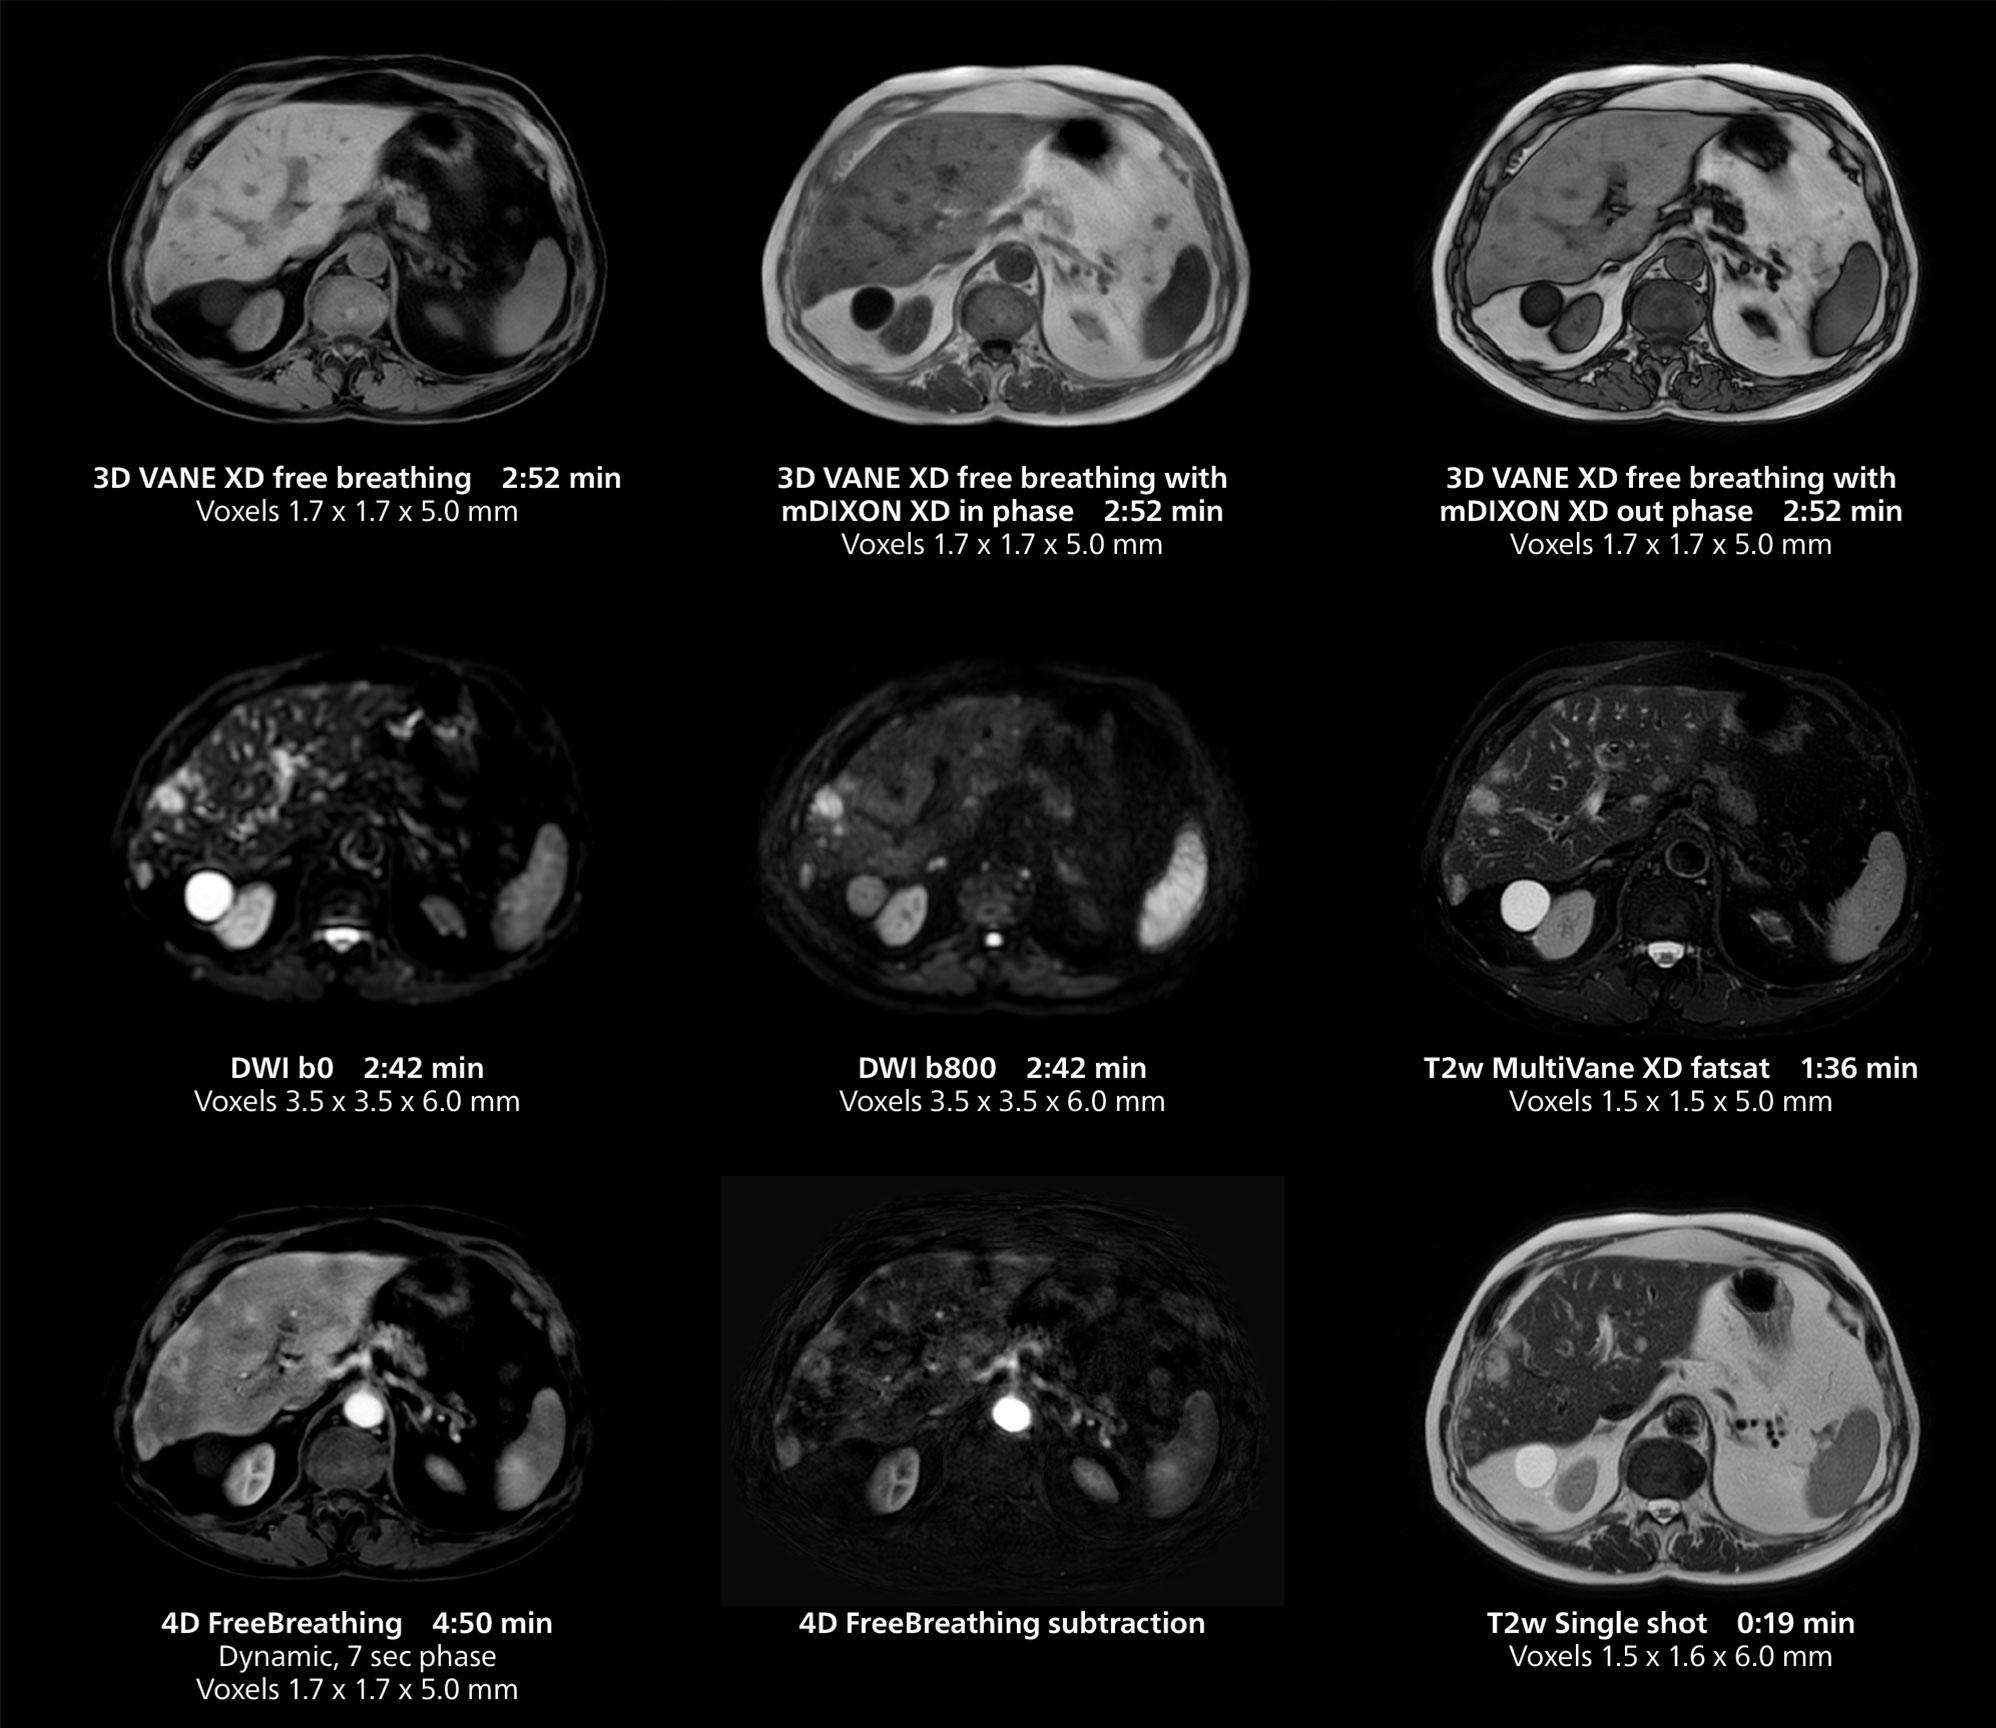

Liver imaging using MR 5300

This case includes 3D free breathing and 4D dynamic free breathing MRI of a metastasized liver. A high quality fatsat sequence with good resolution is obtained in 1:36 minutes with T2-weighted MultiVane XD.

Liver imaging using MR 5300

This case includes 3D free breathing and 4D dynamic free breathing MRI of a metastasized liver. A high quality fatsat sequence with good resolution is obtained in 1:36 minutes with T2-weighted MultiVane XD.